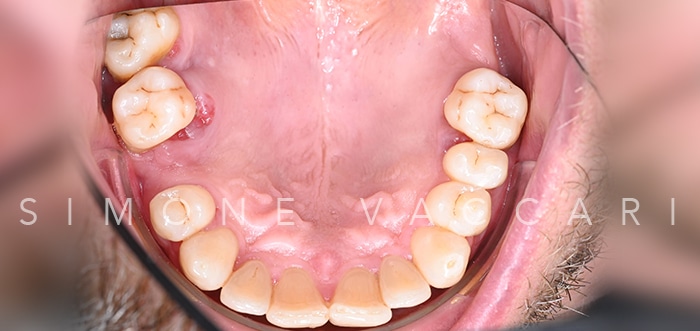

Michele arcata prima della cura della parodontite Prima

Michele arcata dopo la cura della parodontite Dopo